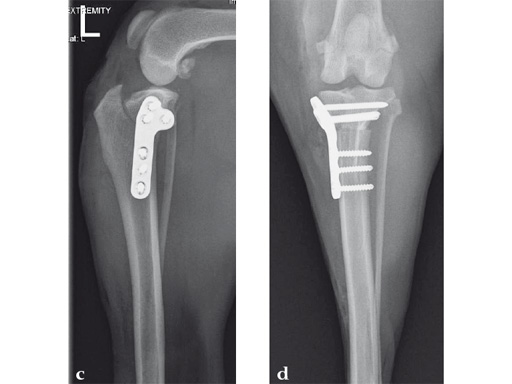

An 11-year-old female, spayed, 13.6 kg cocker spaniel had a complete tear of the left cranial cruciate ligament. A 2.4 mm TPLO plate was perfect for this dog due to the excessive slope of the tibial plateau (30) and the size of the dog. Three 2.4 mm locking screws were used proximally and three 2.4 mm cortical screws were used distally. The contour of this plate matches the contour of the bone almost perfectly. The plate is also designed to optimize the angle of the proximal screws so that they engage the most dense and thickest bone and avoids penetration of the stifle joint.